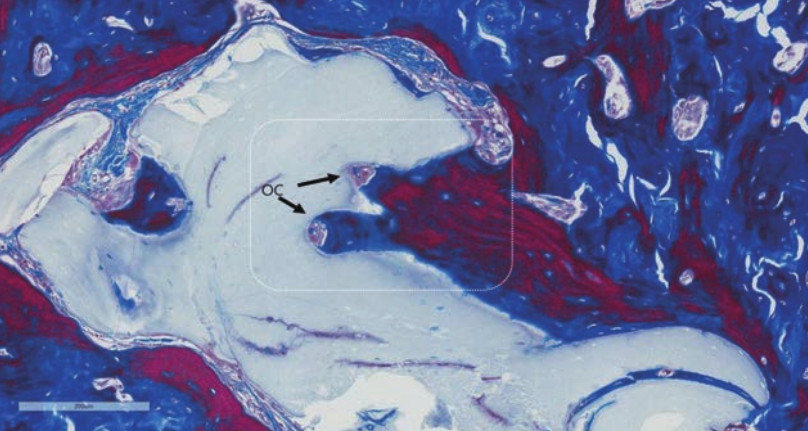

Osteoprzewodzący charakter powierzchni Ti-oss® oceniono na podstawie próbek biopsyjnych.

Konsekwentne tworzenie się nowej tkanki odnotowano w kilku różnych przypadkach klinicznych, dzięki czemu jesteśmy w stanie osiągnąć, przewidywalność i niezawodność procesu regeneracji we wczesnych etapach tworzenie się nowych struktur.

Obserwacja Osteocyte Lacunae

Research Report date: May, 2012 • Kim, Sun Young, D.D.S. Prosthodontist • Suplant Dental ClinicSeoul, Korea

Wyniki biopsji po 3 miesiącach

Wyniki biopsji po 4 miesiącach